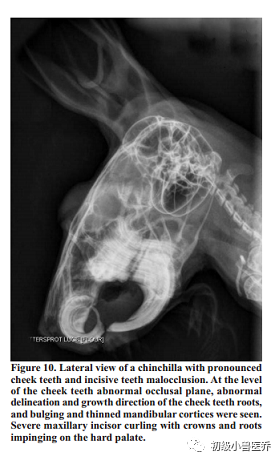

与直接的裸眼的口腔探查相比,口腔内窥镜检查会有更好的质量和口腔内的损伤能更容易观察到。龙猫的口型最适合口腔内窥镜了,因为他们的咬合面是水平的促进了这个检查的进展。这个检查通过看牙龈的大体情况和口腔的粘膜,臼齿临床冠的长度和咬合面的情况,临近空间的大小,和牙齿表面的样子。异常情况像是临床牙冠过长,牙槽和牙峰的改变。臼齿旁舌头和脸颊的偏差(有或没有粘膜破损),和临近牙齿间的宽度增加因此可以见到牙齿间食物的压缩(Capello and Gracis2005)。现在,X光是很常见的基础诊断工具,各种各样的损伤如牙齿重吸收损伤,骨头重吸收和溶解,皮质穿孔,牙根过长,牙齿断裂和缺失都能用X光诊断。但是,需要强调的是正常的X光片不能确定疾病的病理学。很小或特殊的硬组织损伤会被漏诊,直到尸检才被发现(Gracis2008)。放大的X光技术,使用小焦点单位(0.1mm)和一个100mA能量可以作为大小的补偿。一个正常龙猫头颅和牙齿的X光片包括右侧位,背腹位和吻尾位。一个好侧位(LL)可以看到左右侧鼓室,眼眶和下颌关节和腹侧下颌边缘完美重叠(Verstaete2003Gracis2008)。在侧位,本书的作者认为是最有用的一个位置,门齿和切齿都可以评判。上门齿的牙冠不能到达门齿和臼齿间隙长度的2/3,下颚的切齿牙根不能超过第二臼齿(Wiggs and Lobprise1997.门齿咬合表面一般是凿状;,磨损角一般都是上颚的牙齿明显。平坦的咬合面暗示着有牙齿疾病和/或者牙科手术。也有可能是上颌硬腭因为牙齿过度生长而穿孔就会有这个X光影像(Capello and Gracis,2005;Gracis,2008.一般来说,龙猫臼齿咬合面是平整的,差不多是水平的和在侧位片(LL project)上是平行于下颌腹侧边缘的。表面是由光滑的栅栏形成的。为了检查动物是否上颌臼齿过长,要从鼓室的泡门到上门齿背部方向画一条虚拟直线(图9)。如果上颌臼齿牙顶端超过了这条虚线就暗示有这方面的疾病。下颌臼齿尖端很贴近下颌皮质,正常下颌的皮质很薄,很光滑和没有畸形。出现骨头畸形或称之为“突出”强烈暗示下颌臼齿过长。最后,第三种图像(图10)暗示牙冠过长就是上下颌骨间的平行会缺失。背腹部(DV)投影像一般较腹背部(VD)受欢迎是因为背腹部是腹侧摆位,减少了并发呼吸异常的风险。一张好的DVX光应该有一个很完美的对称(在头部左侧和右侧间)。通过这个影像,上下颌骨的边缘,下颌头骨的连接和眼眶的框架都能得到正确评估。异常的像是臼齿过长或生长方向改变都能很容易发现(图11和图12)。另一方面,DV位不适合作为切齿的评估。吻尾位(RC)可以背侧位拍摄(Verhaert2004Capello and Gracis2005.口腔闭合和头部垂直向上与颈部成90度。Bohmer建议开口的RC位,尤其是在评估上臼齿生长过长和颞下颌关节(Bohmer2001a2001b)。RC位提供补充的信息,促进了三个空间去弄明白可能的疾病病理。能明显的观察到牙刺和钉齿,桥接,牙冠和牙尖的生长过长或皮质穿孔。臼齿的角度和咬合面都能测量到。